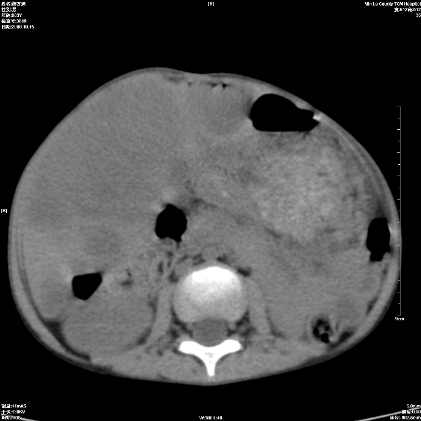

标题: PED1609:男性,3岁。彩超示肝Ca.

3岁;肝低密度灶;有钙化;有转移灶;考虑肝母细胞瘤;查afp

考虑神经母细胞瘤并肝转移